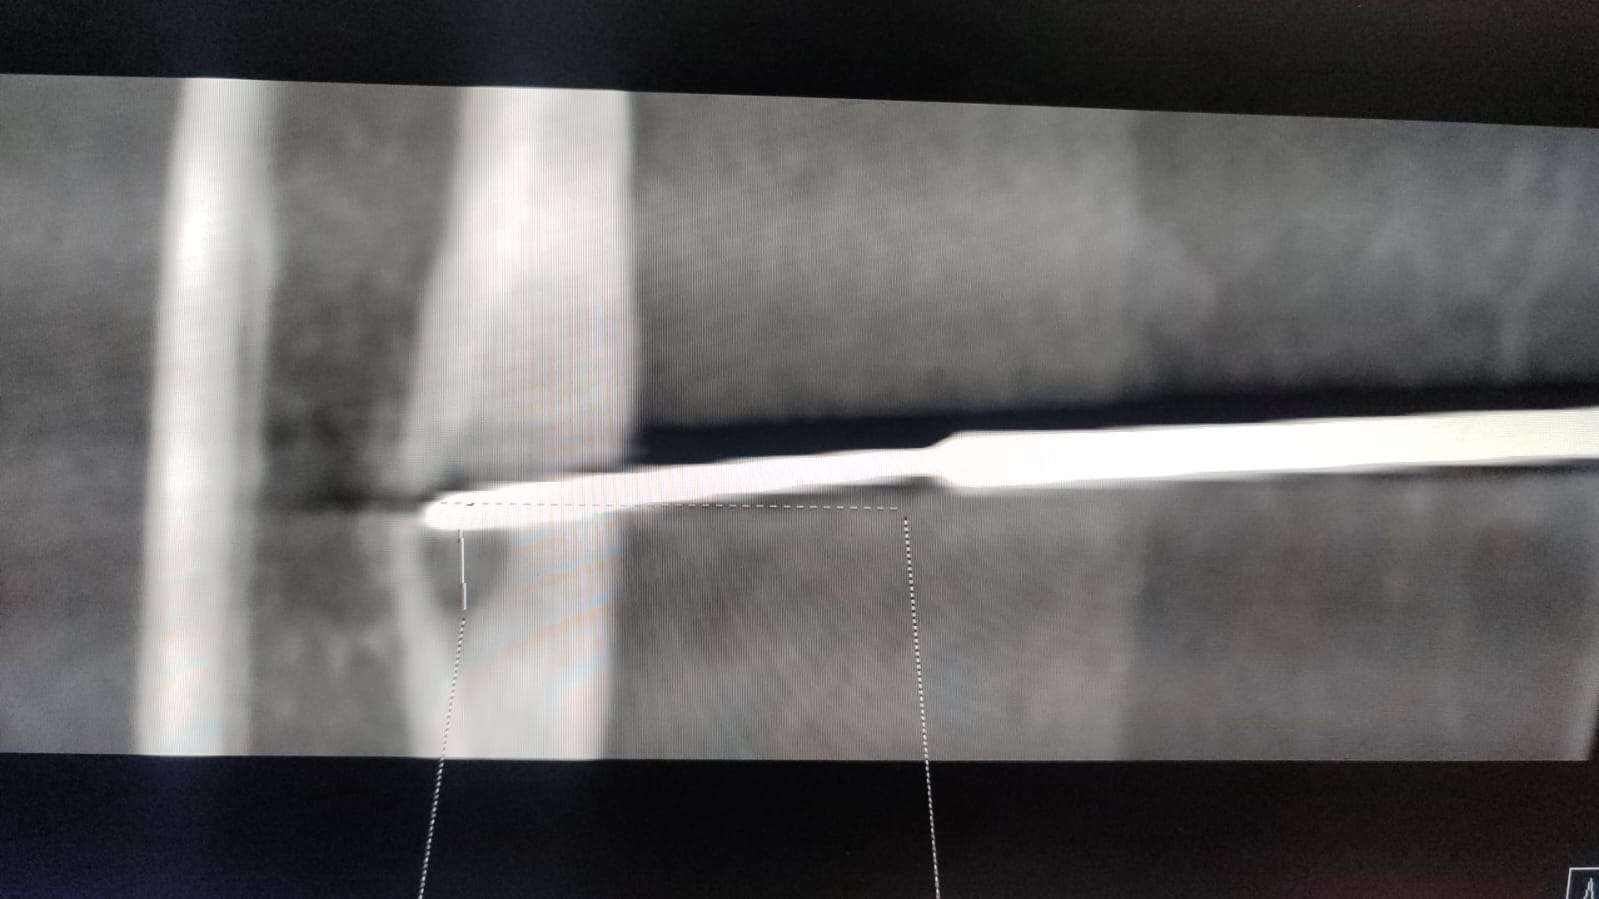

ડૉ.વિકાસ જૈન (સીનિયર કન્સલ્ટન્ટ- ઈન્ટરવેન્શનલ રેડીયોલોજીસ્ટ, વોકહાર્ટ હોસ્પિટલ્સ, રાજકોટ)એ જણાવ્યું હતું કે, “બાળકના સીટી સ્કેન અને એમઆરઆઇમાં જોવામાં આવ્યું કે તેને ડાબા પગના જાંઘના હાડકા (FEMUR BONE)માં ઓસ્ટોઈડ ઓસ્ટીઓમા (Osteoid Osteoma) નામનું ટ્યુમર છે. અમે ઈન્ટરવેન્શનલ રેડિયોલોજીમાં રેડિયો ફ્રિક્વન્સી એબ્લેશનની પદ્ધતિથી સારવાર કરવાનું નક્કી કર્યું અને તેનાથી 5-6 મિલીમીટરના હોલથી આ ગાંઠ સુધી પહોંચી ને એને બાળી નાખવામાં આવી. બાળકે 48-72 કલાકમાં દુ:ખાવામાં પૂર્ણ રાહત મેળવી અને રોજિંદા કાર્યોમાં પરત ફરી શક્યો.”

ઓસ્ટોઈડ ઓસ્ટીઓમા (Osteoid Osteoma) એ એક પ્રકાર નું હાડકાનું ટ્યુમર છે. આ મોટે ભાગે 10-20 વર્ષના લોકોમાં જોવા મળે છે. એમાં રાતના સમયે સુઈ ના શકાય એવો અસહ્ય દુઃખાવો થાય. આ ગાંઠથી જીવનો જોખમ અને શરીરમાં બીજે આ ગાંઠ નો ફેલાવો થતો નથી પરંતુ વ્યક્તિની રોજિંદી ક્રિયાઓ સાવ બંધ થઈ જાય. રેડિયો ફ્રીક્વન્સી એબ્લેશનથી હાડકું કાઢ્યા વગર જ ટ્યુમરને બાળી નાખવા માં આવે. રેડિયો ફ્રીક્વન્સી એબ્લેશન અને માઇક્રોવેવ એબ્લેશન જેવી આધુનિક ટેકનલોજી દ્વારા થાઇરોઇડ, લિવર, કિડની, હાડકું વગેરેના કેન્સર/ગાંઠની સચોટ સારવાર મોટું ઓપરેશન વગર થઈ શકે છે. સમયસર ઈન્ટરવેન્શનલ રેડિયોલોજીસ્ટનો સંપર્ક કરીને ગાંઠ વધે એ પેહલા તેને મૂળ માંથી નષ્ટ કરવાના પ્રયત્નો કરવા જોઈએ કે જેથી દર્દી ને રાહત મળી શકે.